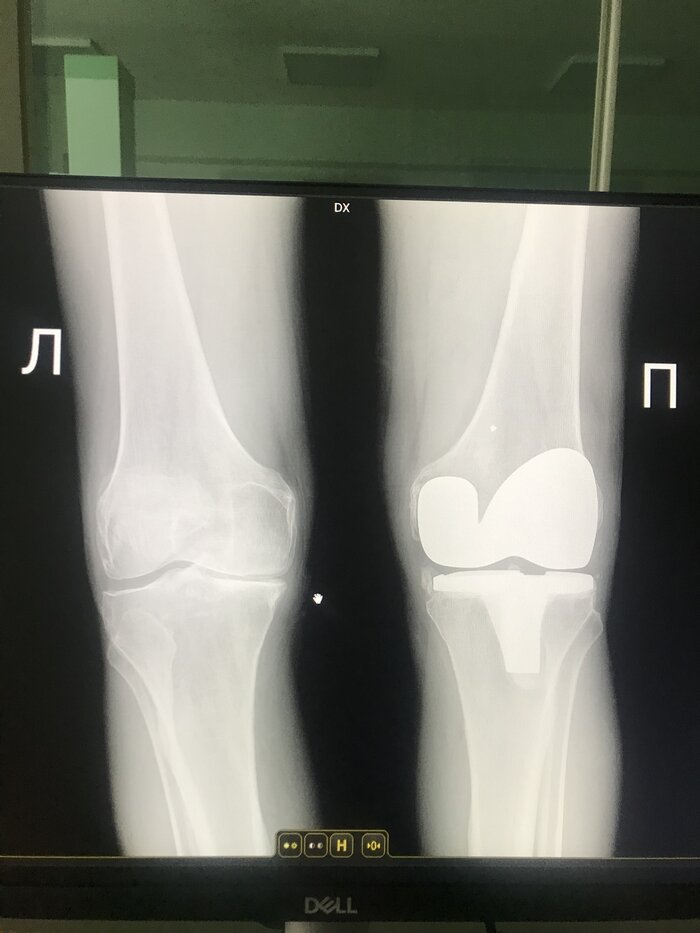

Продукт спорта, человек занимался шорт-треком всю жизнь.

Это он же!)) возраст 70 лет, мужчина.